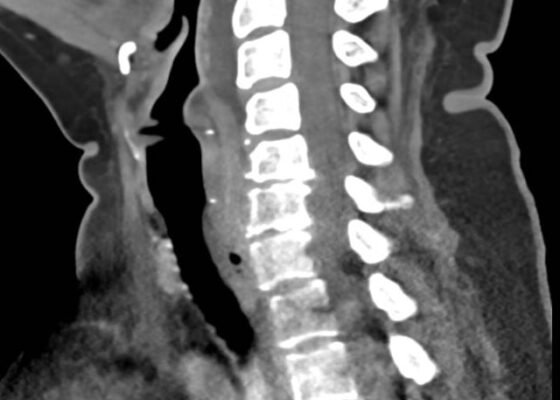

Retropharyngeal Abscess in an Adult Patient Presenting with Neck Fullness and Dysphagia: A Case Report

DOI: https://doi.org/10.21980/J8M36GContrast-enhanced CT soft tissue of the neck showed evidence of a prevertebral/retropharyngeal fluid collection, extending from the odontoid tip to the inferior C4 vertebral body margin, measuring 5.4 x 1.0 x 3.3 centimeters (cm) in size (yellow lines) without gross airway narrowing.